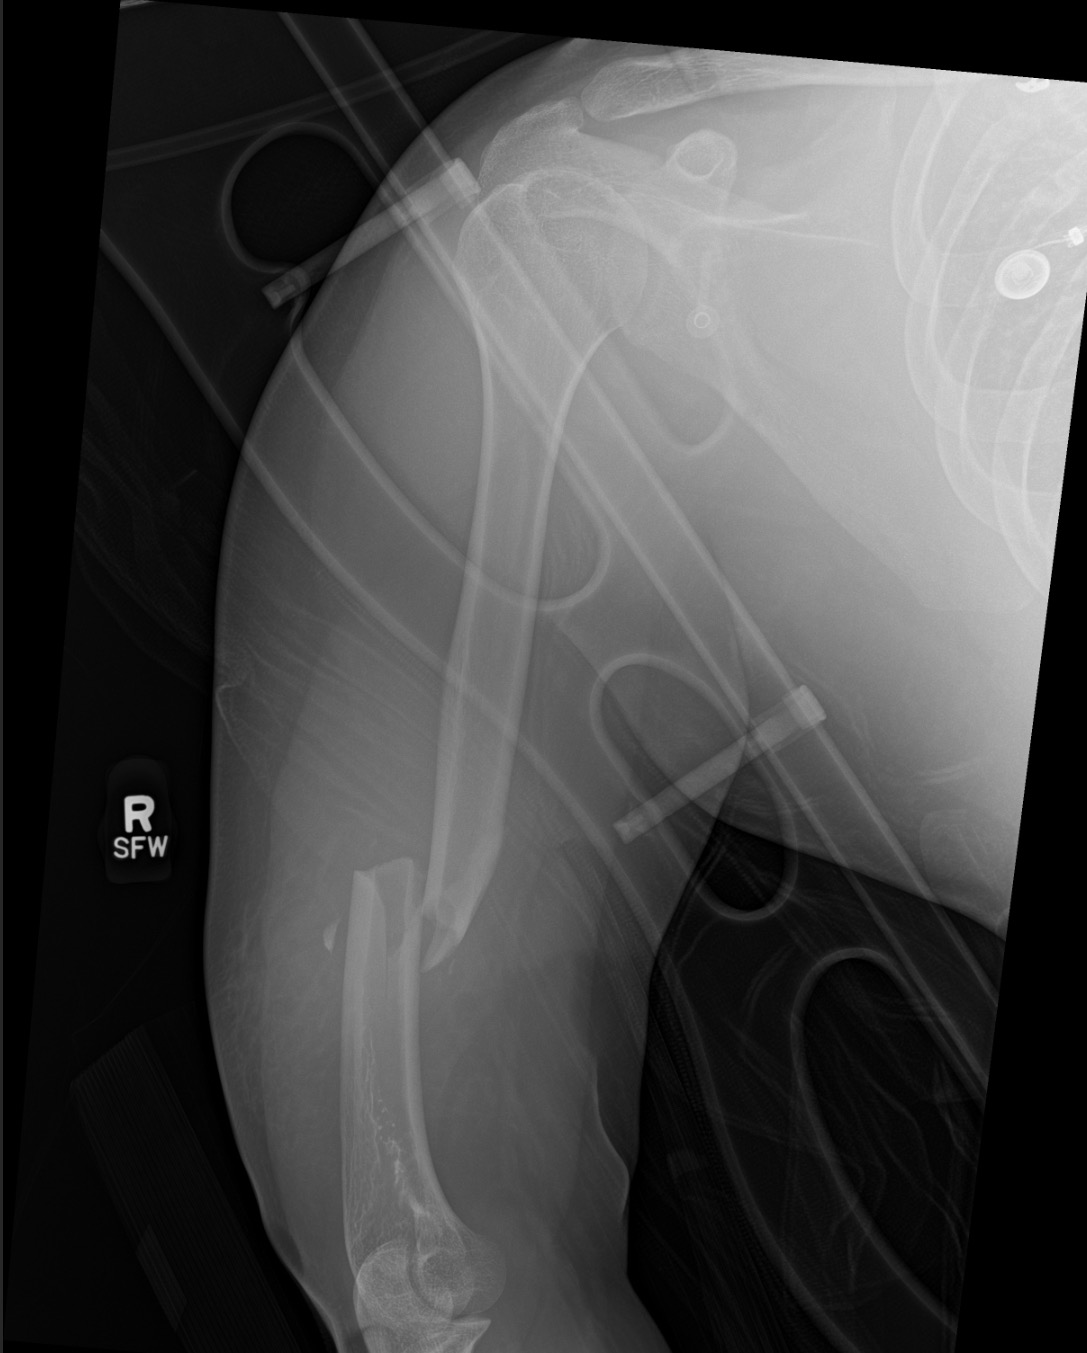

On January 29th Lily’s car lost control after hitting an icy patch on the way to work. Her car flipped and hit a tree. She sustained multiple injuries in her spine, a broken femur (left leg) and humerus (right arm), as well as suffering from a collapsed lung. She was in trauma care for over 2 weeks and will be moved to a physical therapy rehab until she learns to walk again. She is unable to take care of herself at the moment and won’t be able to return to work anytime soon.